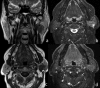

Our aim was to define typical magnetic resonance (MRI) findings in malignant and benign parotid tumours. This study is based on retrospective evaluation of pre-surgical MRI of 94 patients with parotid gland tumours. Histology results were available for all tumours. There were 69 cases of benign (73%) and 25 cases of malignant (27%) tumours, including 44 pleomorphic adenomas, 18 Warthin's tumours, 7 various benign tumours, 6 squamous cell carcinomas, 3 carcinoma ex pleomorphic adenomas, 2 mucoepidermoid carcinomas, 1 adenoid cystic carcinoma and 13 various malignant tumours. The following MRI parameters were evaluated: shape, site, size, margins, signal intensity (SI) on T1w and T2w images, contrast enhancement, signal of cystic content, presence or absence of a capsule, perineural spread, extraglandular growth pattern and cervical adenopathy. Statistical analysis was performed to identify the MRI findings most suggestive of malignancy, and to define the most typical MRI pattern of the most common histologies. Ill-defined margins (p < 0.001), adenopathies (p < 0.001) and infiltrative grown pattern (p < 0.001) were significantly predictive of malignancy. Typical findings of pleomorphic adenoma included hyperintensity on T2w images (p = 0.02), strong contrast enhancement (p < 0.001) and lobulated shape (p = 0.04). Typical findings of Warthin's tumour included hyperintense components on T1w images (p < 0.001), location in the parotid inferior process (p < 0.001) and mild or incomplete contrast enhancement (p = 0.01). SI on T1w and T2w images and contrast enhancement enables differential diagnosis between pleomorphic adenoma and Warthin's tumour.